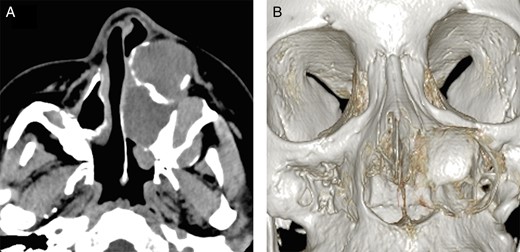

Computed tomographic appearance. (A) Axial computed tomographic section showed a well-defined trilocular cyst in the left maxillary region extending to the cortical plate. (B) Three-dimensional computed tomographic image showing a defect in the nasal lateral wall.